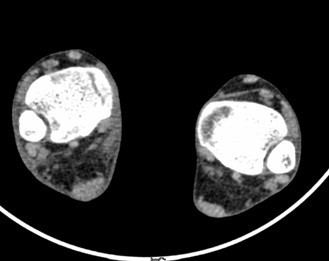

患者男,15岁,因“车祸致右足跟部皮肤撕脱伤清创缝合术后13天”入院。患者13天前因车祸导致右足疼痛流血伴功能障碍,右足跟部皮肤撕脱,遂到当地人民医院就诊,诊断为右跟骨骨折伴跟部皮肤严重剥脱伤,右胫骨远端骨折。急诊下行“右足跟部皮肤严重剥脱伤皮肤严重挫裂伤清创缝合术”。术后给予止痛、消肿、预防感染等对症处理,目前右足外侧及跟部皮肤变暗,坏死。患者为进一步诊疗,故转入我科继续治疗。

查体:右足内踝、外踝及跟部皮肤变暗,部分缺血坏死。未见畸形,稍肿胀。右足趾皮温无明显降低,右足趾感觉未见明显异常。右足内踝、外踝及跟部皮肤局部压痛。右踝关节活动受限,右踝关节活动诱发疼痛。右膝关节活动未见明显异常。 辅查:x片示右跟骨,右胫骨远端骨折。